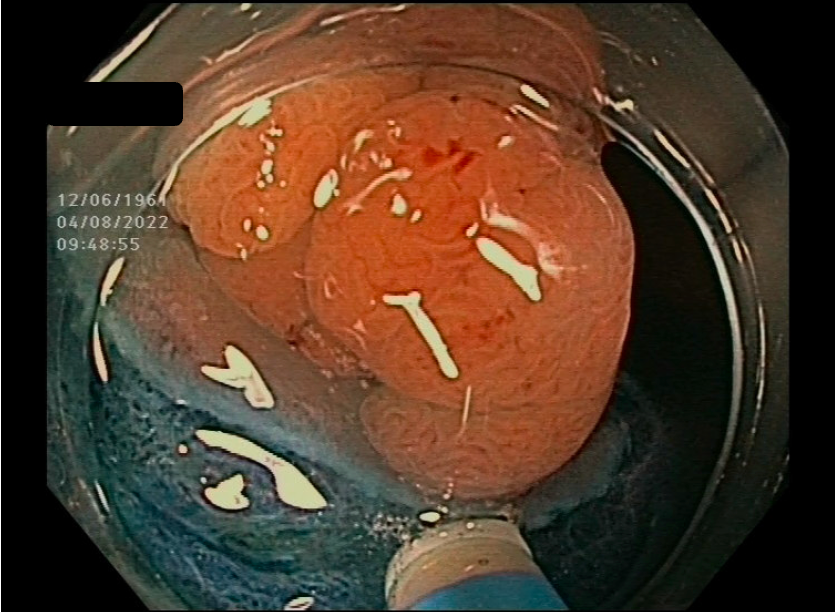

Wie funktioniert die ESD? Die ESD wird durchgeführt, indem ein Endoskop mit speziellen Werkzeugen durch den Mund oder den Darmausgang eingeführt wird. Unter Sichtkontrolle des Endoskops wird dann das erkrankte Gewebe präzise von der darunterliegenden Schleimhautschicht abgetragen.

Was ist die ESD und warum wird sie angewendet? Die endoskopisch submukosale Dissektion (ESD) ist eine innovative Technik, die dazu dient, Frühstadien von gastrointestinalen Tumoren oder andere gutartige Läsionen im Magen-Darm-Trakt präzise zu entfernen. Sie ermöglicht die Entfernung von Gewebe aus der Schleimhautschicht des Verdauungstrakts.